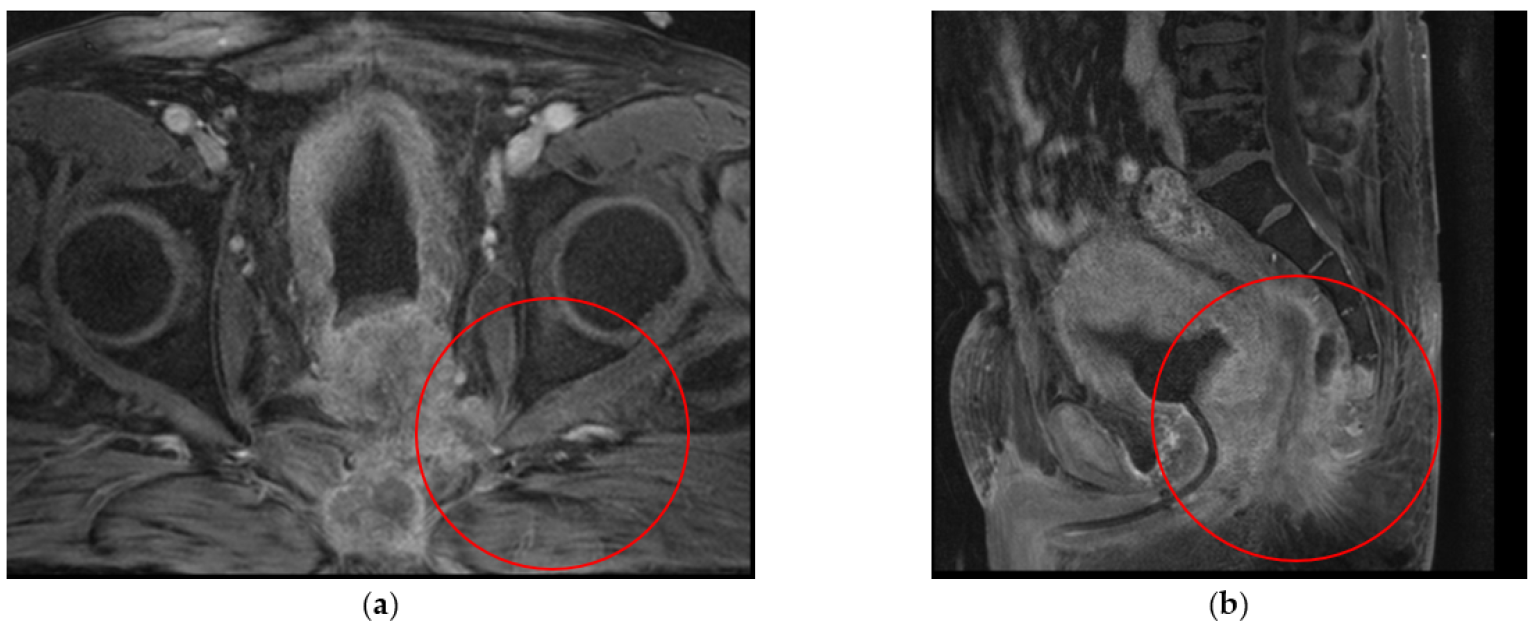

3.1. Clinical Experience in Cases with Invasive Markers

3.2. Clinical Experience in Cases with Noninvasive (Skinbased) Markers